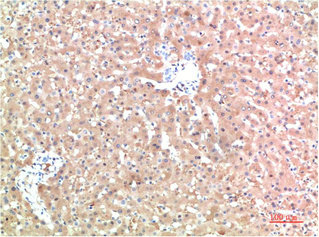

• Immunohistochemical analysis of paraffin-embedded Human Liver Carcinoma Tissue using TTR Mouse mAb diluted at 1:200